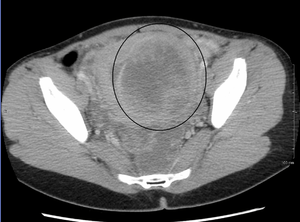

While palpation used in a pelvic examination can typically identify the presence of larger fibroids, gynecologic ultrasonography (ultrasound) has evolved as the standard tool to evaluate the uterus for fibroids. Sonography will depict the fibroids as focal masses with a heterogeneous texture, which usually cause shadowing of the ultrasound beam. The location can be determined and dimensions of the lesion measured. Also magnetic resonance imaging (MRI) can be used to define the depiction of the size and location of the fibroids within the uterus.

A very large (9 cm) fibroid of the uterus which is causing pelvic congestion syndrome as seen on CT